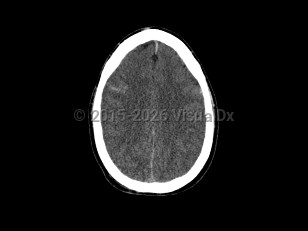

Cerebral edema

Cerebral edema is characterized by blurred vision, intracranial hypertension, headache, and loss of consciousness. Other common signs and symptoms are nausea, vomiting, sudden elevated blood pressure, mental status alteration, and decreased heart rate. It presents a life-threatening medical emergency leading to herniation, coma, and brain death.

Causes include severe brain trauma, ischemic stroke, meningitis, encephalitis, hepatic encephalopathy, brain cancer, diabetic ketoacidosis, eclampsia, or cerebral infarction. It also occurs as a form of high-altitude edema. Cerebral edema may occur in infants and adults.